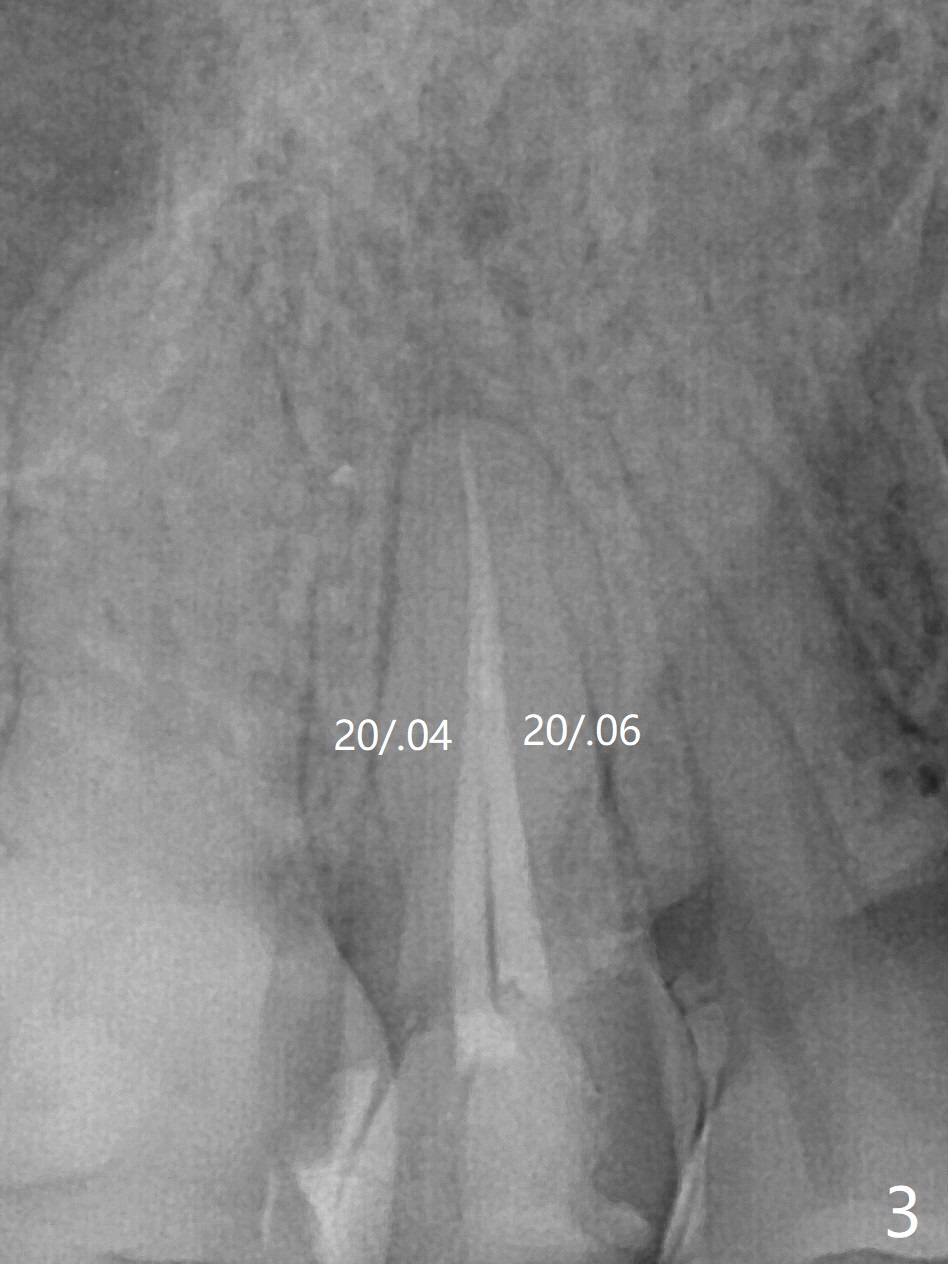

52岁女去年在外州开始4号牙根管治疗(图一),由于新冠病毒和搬家而拖延治疗,现在要求完成根管治疗(图二,三),B: 颊侧(主牙胶尖:20/.04);L: 舌侧(旋转锉:20/.04)。Shining口扫(图四(咬合面观),五(舌侧观),六(颊侧观;对合:局部托牙 (RPD)))。为了保险起见,要求实验室制作两个牙冠:取模,口扫。帮助实验室建立完善数字化系统,从而帮助临床工作。备牙边缘清晰(图八)。牙冠边缘与数字模型(图九)和牙齿吻合,天衣无缝。

Root canal therapy (RCT) was initiated for the tooth #4 of a 52-year-old lady out of state approximately 8 months earlier (Fig.1). The patient requested finishing the treatment and permanent crown fabrication. The buccal (Fig.2 B (master cone 20/.04)) and lingual (L (rotary file 20/.04))) canals fuse near the apex. RCT was done with insertion of 20/.04 and 20/.06 master cones in the buccal and lingual canals, respectively, followed by composite build-up (Fig.3). With basically shoulder margin (not feather margin, chamfer margin ok), it is easy to scan (Fig.4-6 (RPD: removable partial denture)). Return to Oral Scanner Xin Wei, DDS, PhD, MS 1st edition 06/05/2021, last revision 06/25/2021